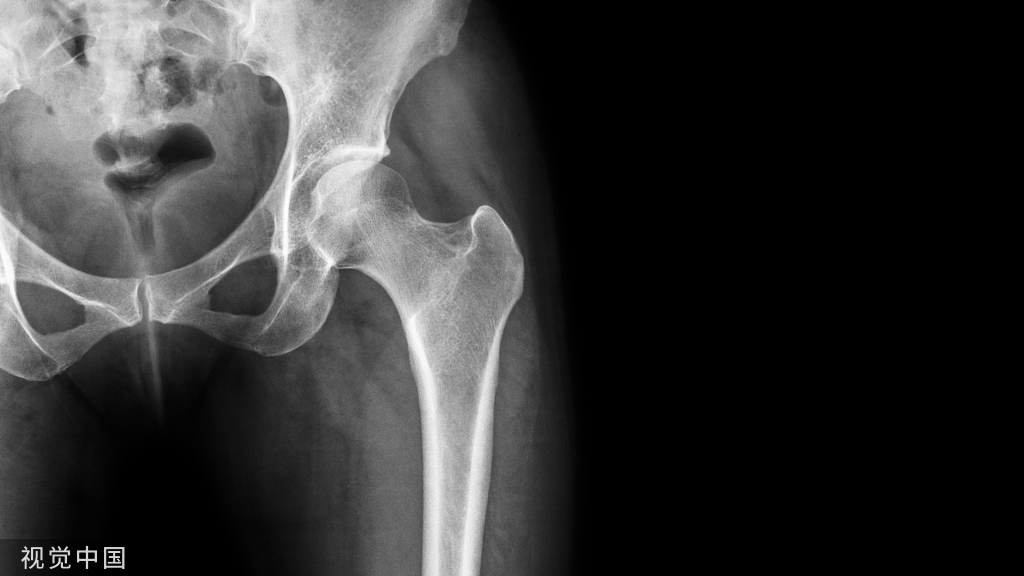

骨质疏松患者晒太阳可以有效补充维生素 D?

随着人类寿命的延长和老龄化社会的到来,骨质疏松发病率逐年增加,已成为人类的重要公共健康问题。骨质疏松患者在使用抗骨质疏松药物的同时,还要根据维生素 D 水平决定是否需要补充维生素 D。

由于维生素 D3 和维生素 D2 是骨骼代谢的重要物质,能够促进小肠对钙的吸收并促使骨骼的形成,所以说晒太阳能补充维生素 D,还可以补钙,预防和改善骨质疏松。